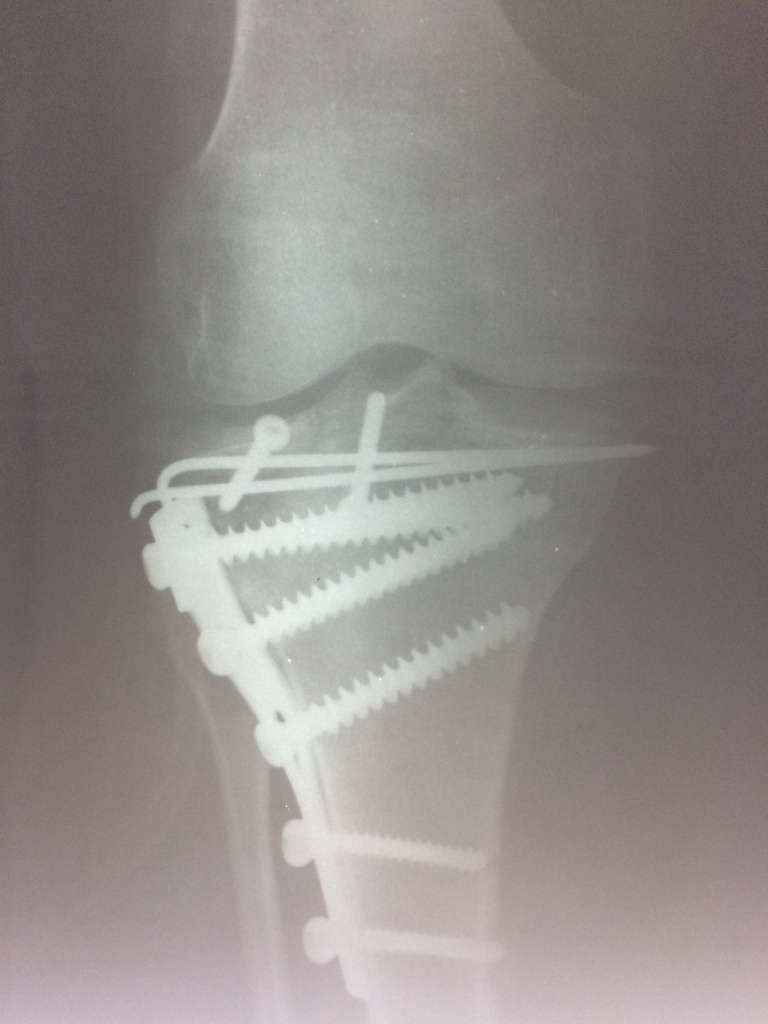

Использование материала Остеоматрикс при импрессионном оскольчатом переломе наружного мыщелка большеберцовой кости по типу Schatzker II

Использование материала Остеоматрикс при импрессионном оскольчатом переломе наружного мыщелка большеберцовой кости по типу Schatzker II.

Операция - открытая репозиция, остеосинтез большеберцовой кости опорной пластиной с костной ксенопластикой маетриалом "Остеоматрикс". На контрольных снимках в три и шесть месяцев имеется консолидация перелома, миграции фиксатора нет, имеется остеоинтеграция ксенопластического материала. Функция коленного сустава полная.